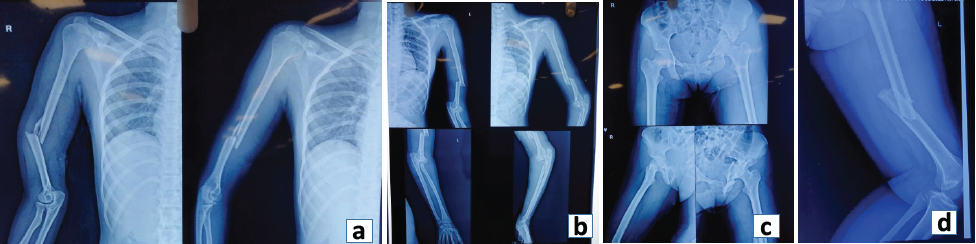

An 18-year-old female fell from a height of 20 feet on June 19th, 2022 and presented with complaints of pain and swelling over the bilateral distal arm and elbow, pain over the left hip and thigh, and inability to bear weight. Clinical examination showed a 2 × 2 cm open wound over the right distal arm and tenderness over the bilateral distal arm and left mid-thigh and hip. Three-point relationship over the left elbow was distorted and the pelvic compression test was positive. Initial resuscitation was done as per the advanced trauma life support Protocol. Based on clinical and radiological evaluation patient was found to have multiple upper and lower limb fractures, which are:

- Open shaft of humerus fracture right side (AO12B2) (Fig. 1a)

- Complex elbow fracture-dislocation (terrible triad) with shaft humerus fracture (AO12A2) left side (Fig. 1b)

- T-type Acetabulum fracture on the left side with bilateral superior and inferior pubic rami fracture (Fig. 1c)

- Shaft of femur fracture left side (AO32A2) (Fig. 1d)

Figure 1: (a) Pre-operative X-ray showing the shaft of the humerus fracture right side (AO12B2), (b) Pre Op X-ray showing complex elbow fracture-dislocation (terrible triad) with shaft humerus fracture (AO12A2) left side, (c) T-type Acetabulum fracture left side with bilateral superior and inferior pubic rami fracture, (d) Shaft of femur fracture left side (AO32A2).